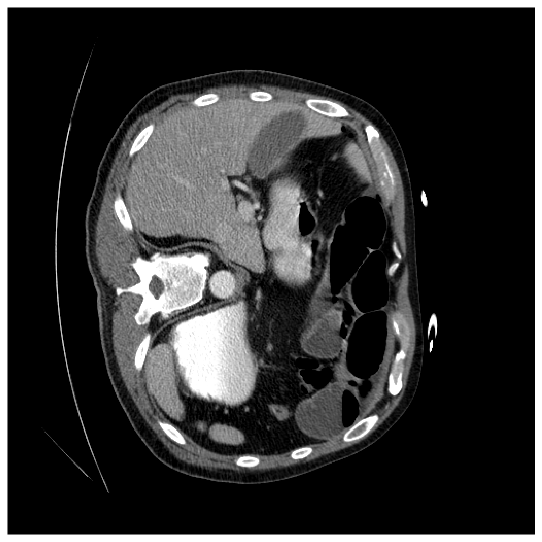

where and denote the fuzzy window patch extracted from the original image and the pixel at coordinates in the original image , respectively. is the scaling factor defined as the ratio of the desired uniform variance to the fuzzy variance , and is the translation factor, where represents the fuzzy mean. In the logarithmic model, the operator represents scalar multiplication. The membership function calculator, , is weighted based on how each transformed fuzzy window contributes to the final enhanced image. As a result, the enhanced image exhibits improved quality and a distinct feature distribution compared to the original image. The original and enhanced images are shown in Fig. 14(a) and Fig. 14(b), respectively. As shown in Fig. 14(b), the image quality is enhanced by Eq. (12), emphasizing the organ’s attributes, including shape and intensity. Consequently, previously subtle features in Fig. 14(a), become more pronounced in Fig. 14(b). When these two images are processed through their respective encoders, they generate feature maps characterized by diverse feature distributions and unique information. In other words, the boundary information is better preserved in the original image, while the enhanced image highlights the object’s details. Thus, cross-learning the information from both images leads to improved performance. Please kindly refer to [36] for more details.